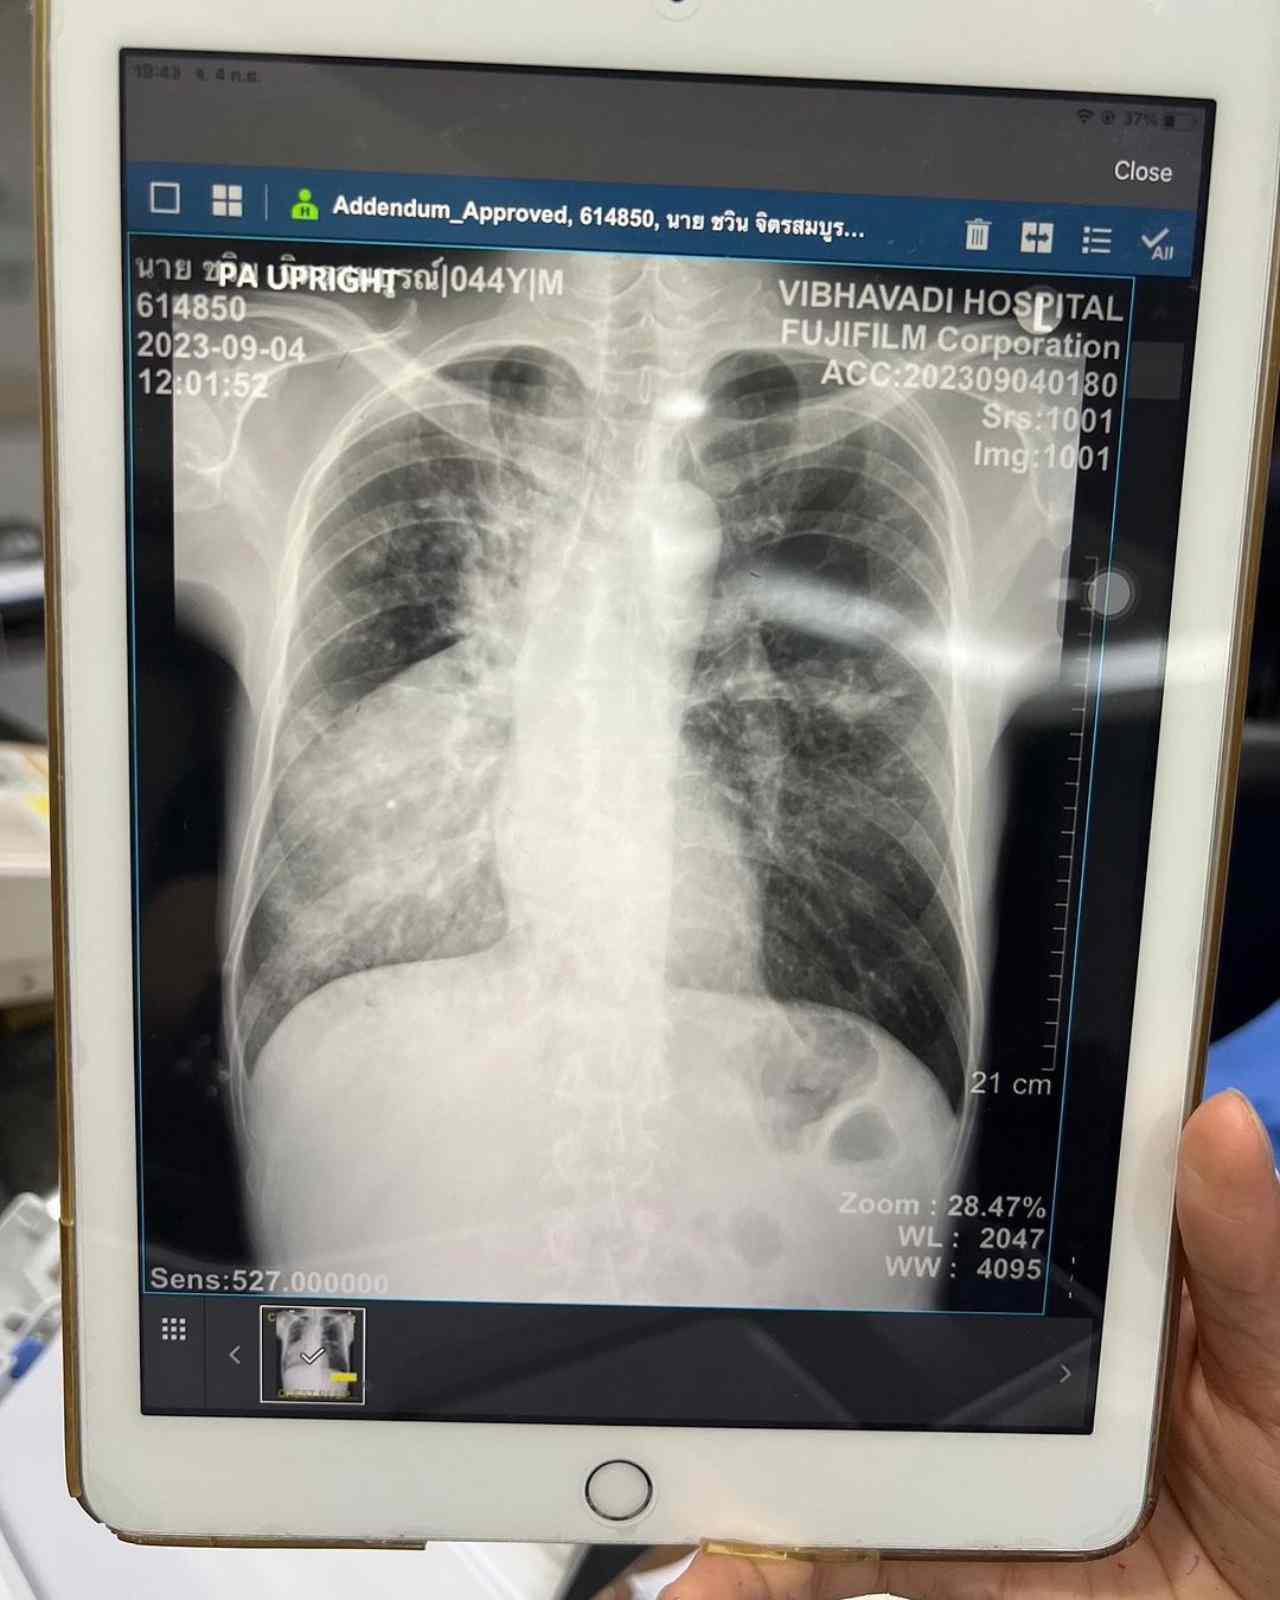

แต่ว่าเชื้อนั้นอาจใช้เวลาเพาะเป็นปี หรือ 10 ถึง 20 ปีก็ได้ สรุปคือวัณโรครับประทานปอด ยังดีที่รู้เร็วก็รักษากันไป น่าจะได้นอนอยู่โรงบาลหลายวัน แคนเซิลงานไปแล้วบางส่วน ส่วนเพื่อนเพื่อนพี่น้องที่จะมาเยี่ยม กรุณาใส่หน้ากาก N95 เท่านั้นนะครับ #จั๊กชวิน #ระนะจั๊ก_รักนะจ๊ะ"